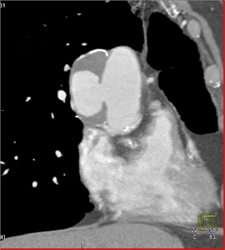

Diagnosis

Type A Dissection